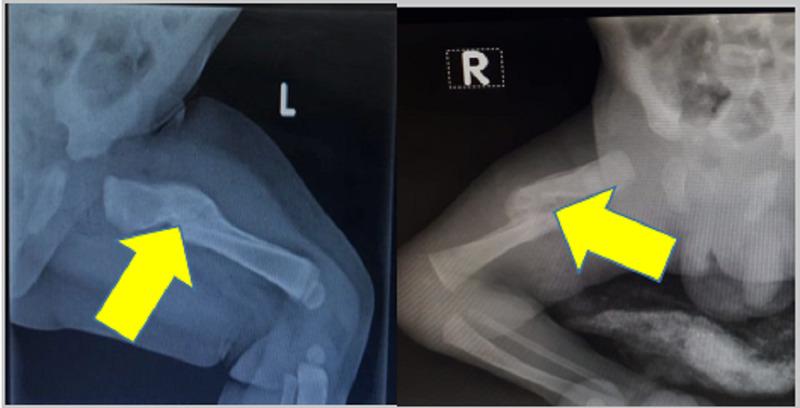

新生儿股骨干骨折:两例报告

Femur Shaft Fracture in Newborns: A Report of Two Cases.

Birth injuries caused by trauma during the childbirth process are very rare. They are a cause of significant neonatal morbidity despite improved obstetric and perinatal care, particularly in developing countries. Our current research, consisting of two newborns with a femur fracture, aims to shed light on their treatment strategy.

摘要